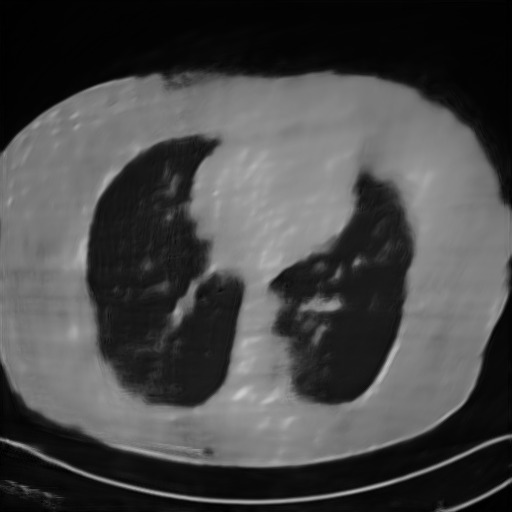

We further increase the noise level contained in the raw data to 10% white Gaussian noises and list the quantitative results in Table IV. It can be observed that the reconstruction performance of the TV model is poor in the case of high-level noises with PSNR dropping by 4 to 5 dB compared to the previous experiments. On the other hand, the performance of the learning-based methods is less sensitive to noises. The SIPID method relying on the sinogram interpolation works better than FBP-Unet. And the deep unrolling methods (i.e., PD-net, IFSR-net, SFSR-net) outperform the traditional iterative algorithm when the scanning range is limited and data is corrupted by noises. Similar to the previous experiments, compared with other deep learning algorithms, our LRIP-nets give the reconstruction results with higher PSNR and SSIM. Moreover, the low-resolution image obtained by the projection data down-sampled with rate 1/8 always gives the best reconstruction results with more than 2 dB PSNR and 0.05 SSIM increments compared to the PD-net. Fig. 6 illustrates the reconstructed images from different methodologies with scanning angular range of and 10% Gaussian noises. It can be seen that the both TV model and the FBP-Unet suffers from significant artifacts, which present distortions in the angular range of the missing scan. Other learning-based methods provides better visual qualities than FBP-Unet, and our LRIP-net1/8 still gives the best reconstruction result with correct boundaries and fine structures.

Fig. 7 manifests the reconstruction results of these methods with scanning angular of . It can be seen that both FBP and FBP-Unet produce serious artifacts within the range of missing angles. The TV model performs well in removing Poisson noises, but it can not handle the artifacts very well. Similarly, there left obvious artifacts on boundaries and different degrees of missing in visceral tissues of the reconstruction images obtained by the SIPID, PD-net and FSR-net. The visceral tissue and boundaries of our LRIP-net reconstructions are more intact and smoother, especially for the LRIP-net1/8 which gives the ideal boundaries. The observation becomes even apparent if we look at the zoom-in regions, where the LRIP-nets can produce results with fine structures. Therefore, we conclude that the low-resolution image prior can effectively improve the qualities of the limited-angle CT reconstruction.